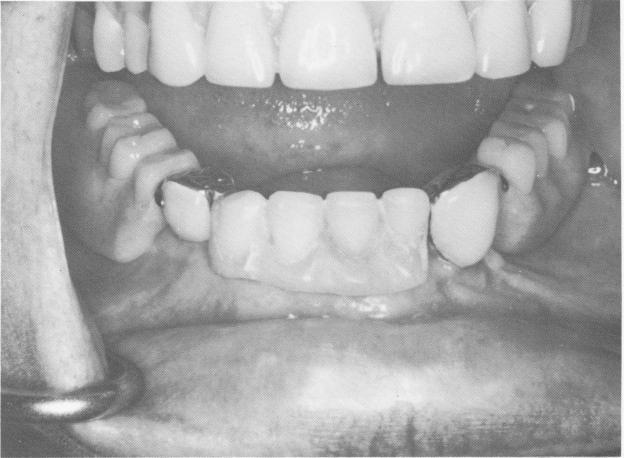

Fig. 5-62. Clinical view of the crowns over the protruding implant posts. (Courtesy R. V Christensen.)

Fig. 5-63. The denture is secured to the implant abutments. (Courtesy R. W. Christensen.)

1 View of crowns over protruding endosseous implant posts in manidble

2 Denture is secured to endosseous implant abutments in mandible